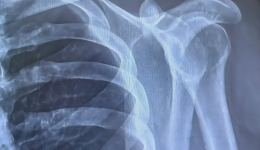

术业求精 | 我院成功开展全关节镜下肩锁关节脱位微创手术

微创手术是21世纪外科的重点发展方向,关节镜手术是一种微创手术,具有手术创伤小、出血少,患者恢复快等诸多优势。近日,山东大学齐鲁医院(青岛)骨科中心运动医学科甘煜东副主任医师带领医疗团队完成了全关节镜下肩锁关节脱位微创手术。该患者为...